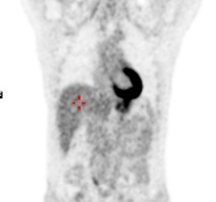

TEP-FDG : persistance d’un discret hypermétabolisme en regard de l’adénomégalie

axillaire droite isolée SUV max 2.0 , SUV max du bruit de fond avoisinant à 0.9.

Absence d’hypermétabolisme suspect au niveau des autres aires ganglionnaires.

Réponse métabolique partielle axillaire droite et réponse métabolique complète

sur les autres territoires.